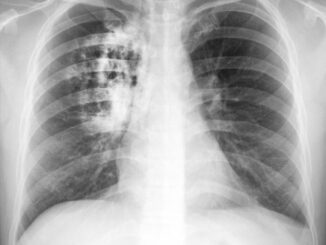

9 SIMPTOMA RAKA PLUĆA NA KOJE TRABATE ODMAH REAGOVATI: Ovako vas tijelo upozorava na ovu bolest!

O sumnjivim simptomima razgovarajte sa svojim liječnikom obiteljske medicine, pogotovo ako su dugotrajni i ne možete ih ublažiti uobičajenim metodama. Kašalj koji s vremenom postaje […]